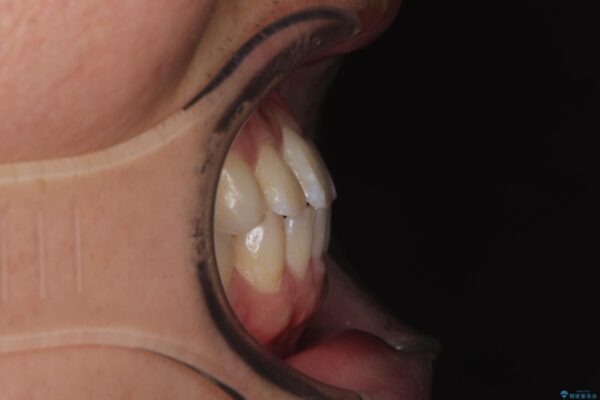

主訴:前歯のデコボコと奥歯のかみ合わせを治したい 今回ご紹介するのは、「前歯のガタガタ(叢生)」と「奥歯のかみ合わせ(シザーズバイト)」にお悩みでご来院された患者様の症例です。 患者様は、 ・歯並びをできるだけ早く改善したい ・費用を抑えた矯正治療 というご要望をお持ちでした。

・上顎左右の第二大臼歯が頬側へ転移し、シザーズバイト(scissors bite)の状態

・上顎左側第二小臼歯が90度捻転しており、噛み合わせに影響

治療途中

• 前歯のガタガタ・奥歯のかみ合わせ(シザーズバイト)を改善|1年半で完了したメタルブラケット矯正 治療途中画像